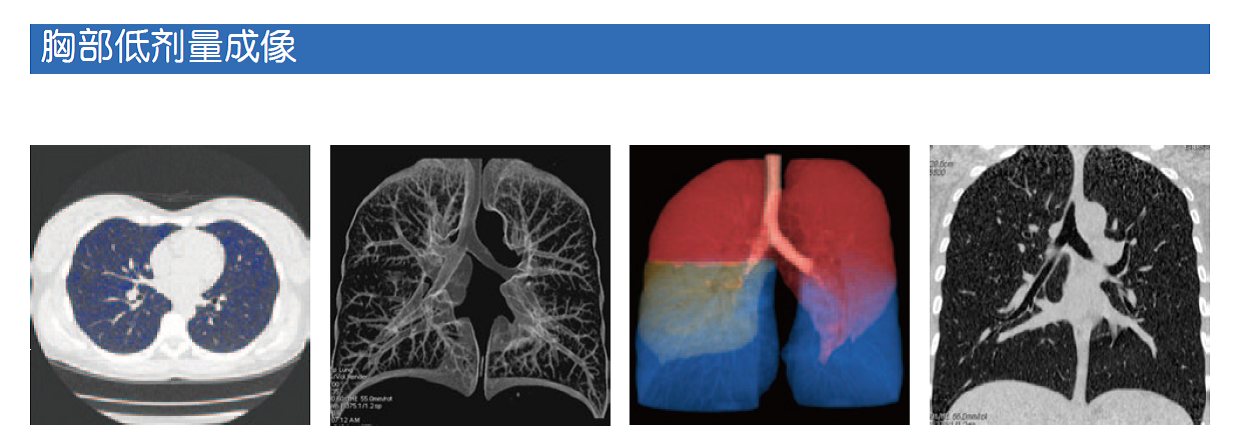

美国全国肺筛查试验(NLST)是一项CT描与胸部X线筛查高危列人群肺癌特异性死亡率的随机试验文“Results of the Two Incidence Screenings in the National Lung Screening Trial20139月发表在国际权威的新英格兰杂志(NEJM。美国加州大学放射科学研究室的Aberle博士等人在论文中得出结论:低CT出早期肺癌有更高的敏感性,但阳性预测值X线摄低。与X线摄相比,利用低CT术进行的两肺癌生率筛查导致晚期肺癌断数量下降,早期肺癌诊断数量上升。

现在放射科对于“关爱患者安全”发展到了如何降低辐射剂量等本质问题上。CT设备生产厂家在不断使用各种先进的前沿技术降低设备检查中的辐射,放射科医生也在尝试通过优化扫描参数的设置降低辐射剂量。